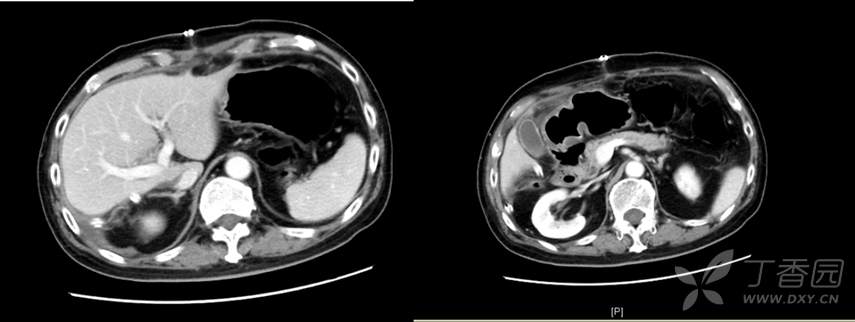

患者术后恢复顺利,7天拆线出院,出院前CT如下: